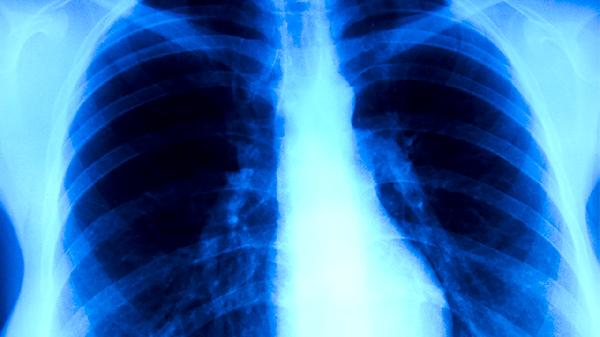

5到15岁的孩子因为免疫系统尚未完全发育,是感染的高发人群。在学校的集体环境中,病毒更容易传播,常常出现班级内集中发病的情况。患儿多表现为持续干咳伴有轻中度发热,肺部检查可能不明显,但胸部X光可见斑片状阴影,需通过血清抗体检测来确诊。